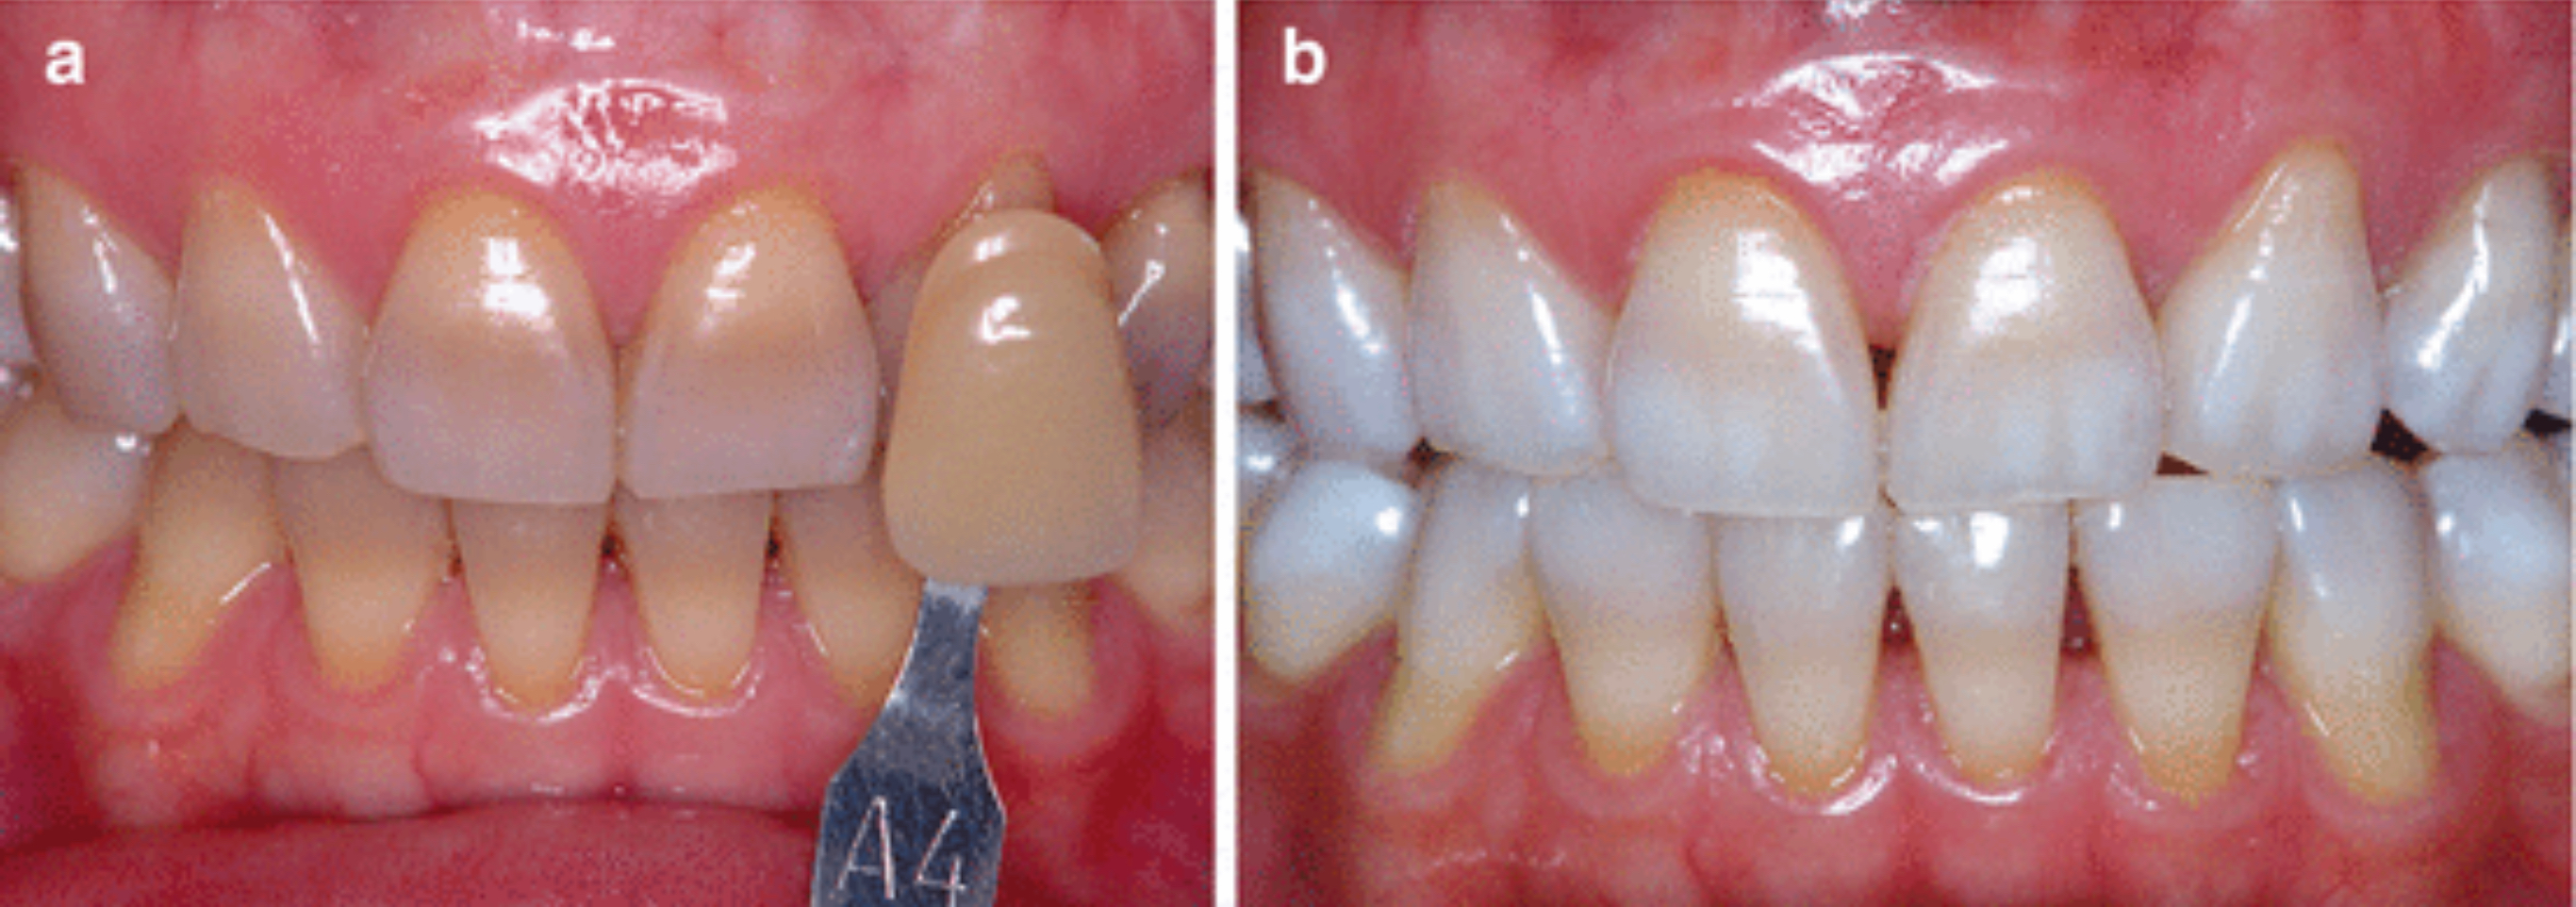

了解與牙周病的發展,也可幫助民眾做簡單的自我檢查,以便早期發現、早期治療。健康的牙齦組織為但淡粉紅色,牙齦結實。一旦牙菌斑累積,初期會引發牙齦炎,此時牙齦外觀紅腫,刷牙時牙齦會出血。當牙齦發炎沒有即時控制治療,牙齦炎將發展至牙周病,病患會發現牙齦明顯退縮、牙縫越來越大、牙齒開始對冷熱酸痛敏感、口臭、牙齒搖動,咀嚼時不如以往紮實有力,甚至會有疼痛感,嚴重者口內會出現化膿現象。